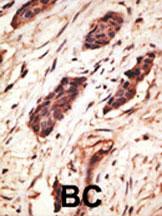

(The image on the left is immunohistochemistry of paraffin-embedded Human lung cancer tissue using AAA241054(SLC11A2 Antibody) at dilution 1/50, on the right is treated with synthetic peptide. (Original magnification: ×200))